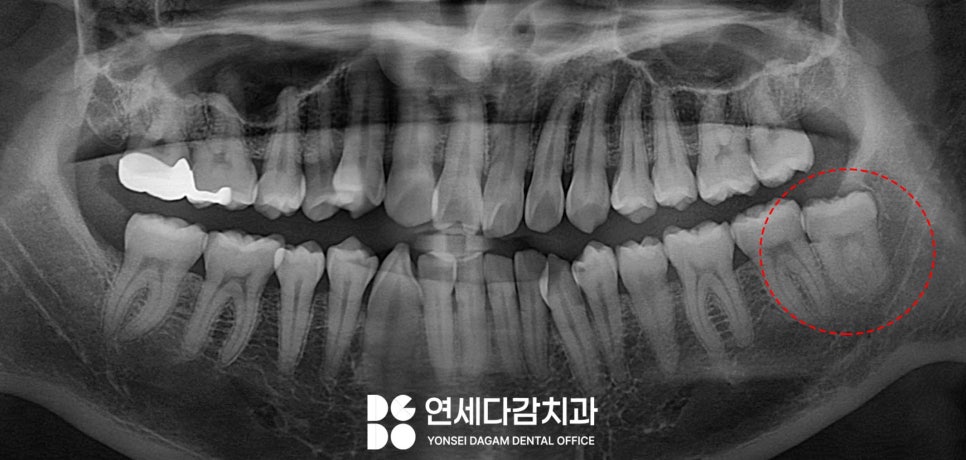

사랑니 상태를 확인할 때

일반적으로 파노라마 엑스레이를 촬영합니다.

파노라마는 턱 전체를 한눈에 볼 수 있어

사랑니의 위치와 방향을

대략적으로 파악할 수 있습니다.

그러나 2차원 영상이기 때문에

한계가 있습니다.

특히 사랑니 뿌리 끝이

하치조신경과 가까워 보이는 경우

실제로 붙어있는지 떨어져 있는지

정확히 알기 어렵습니다.

이럴 때 CBCT 촬영이 필요합니다.